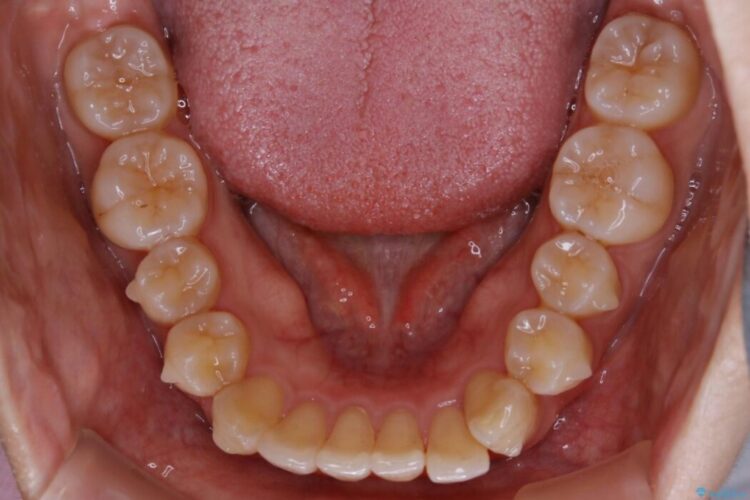

下額前歯が少しガタついていることを気にされて来院されました。

検査をしたところ奥歯の噛み合わせなどに問題が見られなかったため、軽度のねじれがある下顎前歯に焦点を当てた部分矯正の適応が可能と判断し、インビザラインのライトパッケージをご提案しました。